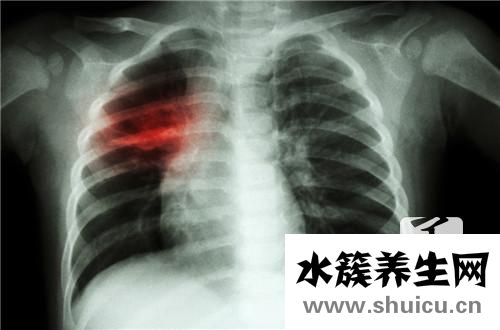

支氣管炎胸膜增厚瘺管是日常生活中人體胸部支氣管的常見疾病。 支氣管炎的癥狀是胸膜增厚性瘺管很容易引起呼吸困難,呼吸困難,也很容易引起咳嗽,痰多,咳嗽或發燒,發燒等,也很容易引起其他疾病,這需要 立...